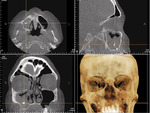

Zanim lekarz stomatolog przystąpi do zabiegów implantacyjnych z podniesieniem dna zatoki szczękowej, należy wykonać diagnostykę radiologiczną – stomatologiczną tomografię stożkową (CBCT), która pozwala na precyzyjną diagnostykę korzeni zębów i zatok przynosowych. Dawka promieniowania jest mniejsza niż w przypadku konwencjonalnej tomografii komputerowej. Badanie to pozwala na dokładną ocenę procesów chorobowych, które mogą być przeciwwskazaniem do planowanego zabiegu stomatologicznego.

Jeżeli istnieją zmiany radiologiczne w zatoce szczękowej, należy pacjenta skierować do laryngologa (ryc. 1).